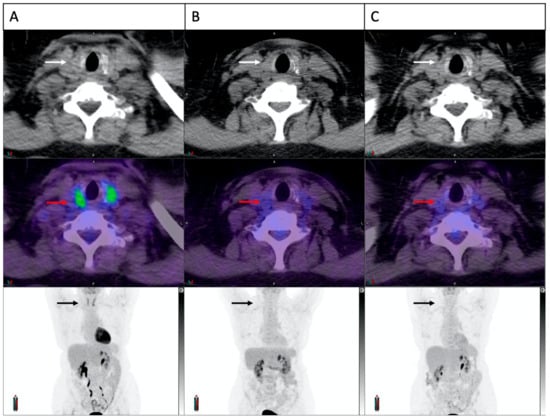

3.5. Concomitant Muscle Uptake